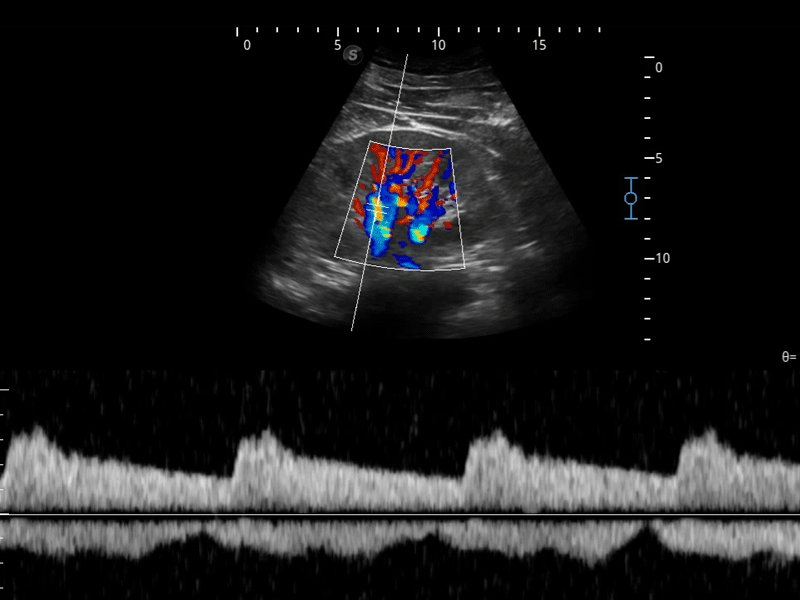

造影成像

造影成像功能和定量分析工具包使医生能够更好的评估血流灌注情况。独特的动态声压控技术有效控制造影剂的声压,保证更长的造影剂持续时间,更好的观察病变灌注的延迟相位。

组织多普勒

组织多普勒成像功能,可提供心肌运动速度和其他临床信息,使临床医生能够分析和比较患者心脏不同部位的运动。

临床图像